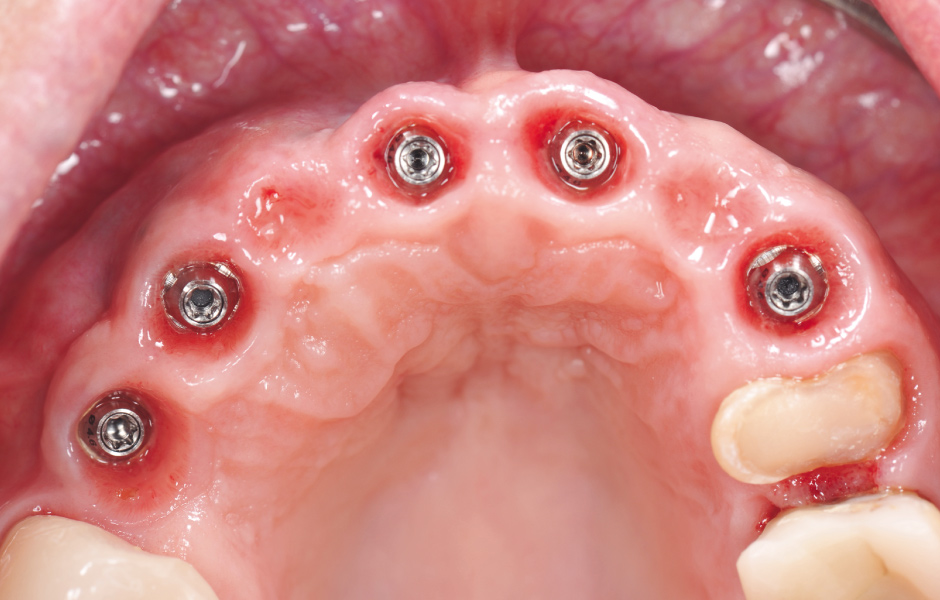

Po požadovaném vytvarování sulku na 3D tištěném pracovním modelu může být zhotoven provizorní PMMA můstek. Provizorní titanové abutmenty umožňují přesný dosed provizorní náhrady na implantáty (obr. 30) (Rutten, Rutten a Holst, 2017) – jsou designovány pro přesné spojení mezi provizorním pryskyřičným můstkem a implantáty a nabízí mechanicky vysoce odolné spojení. Titanové „cylindry“ provizorních abutmentů budou vlepeny do vyfrézovaného pryskyřičného můstku.

Design a přesnost dosedu na gingivu u provizorního můstku musí být zhotoveny s ohledem na vytvoření optimálního emergence profilu a tvarově co nejpřesněji, jako podklad pro následné zhotovení finální keramické náhrady po oseointegraci implantátů a zhojení gingivy (obr. 31, 32).

Pochopení biologického aspektu měkkých tkání je v této fázi velmi důležité. Tvar náhrad v subgingiválních oblastech lze předem prodiskutovat a zhotovit podle pokynů lékaře, aby se předešlo pozdějším problémům. Ideální tvar provizorní náhrady umožní hojení měkkých tkání tak, aby se vytvořila pevná a zdravá gingiva kolem implantátů a zachovala se tak architektura periimplantátových tkání na dlouhou dobu. To vyžaduje úzkou spolupráci mezi lékařem a technikem.

Jeden z nejdůležitějších aspektů u provizorních náhrad je, že oblasti, které jsou v kontaktu s gingivou, by měly být ručně velmi pečlivě vyleštěny, aby se zabránilo retenci a hromadění plaku.